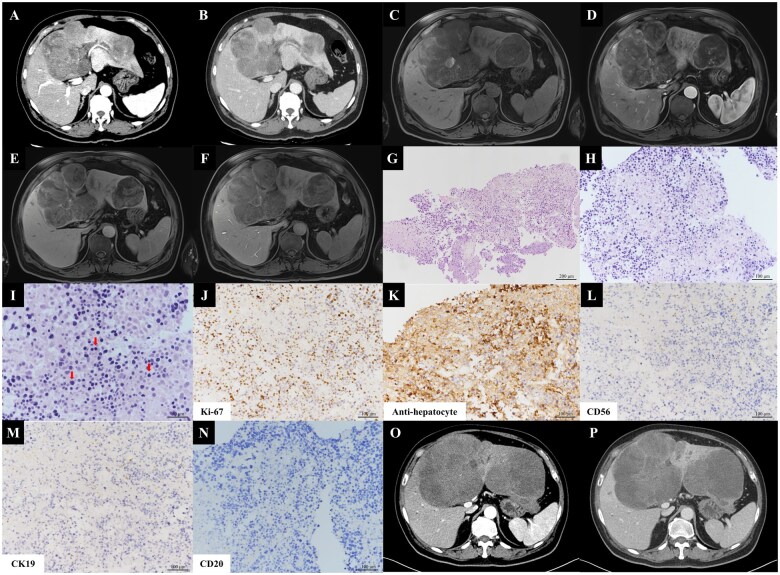

Primary small cell-like hepatocellular carcinoma arising in a patient with fatty liver disease without cirrhosis: a case report and literature review.

无肝硬化脂肪肝患者发生原发性小细胞样肝细胞癌1例报告及文献复习